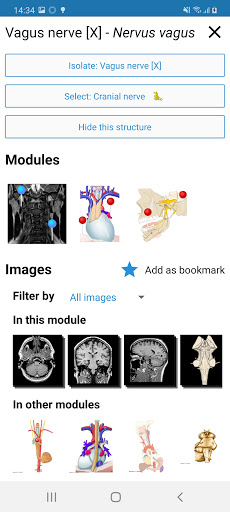

*Improved detail view of anatomical parts for easier identification in images of the current and other modules.

- “Filter by”, in the details view you can now filter the images containing the anatomical structure by modality

- “Filter by”, in the details view you can now filter the images containing the anatomical structure by modality

- You can now hide structures one by one (new button inside the description popup) and display them again in the right menu